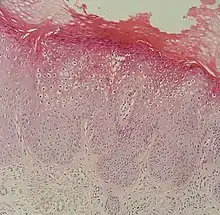

At histopathology, flat warts have cells with prominent perinuclear vacuolization around pyknotic, basophilic, centrally located nuclei that may be located in the granular layer.[4] These are referred to as "owl's eye cells."[4]

Micrograph of a flat wart